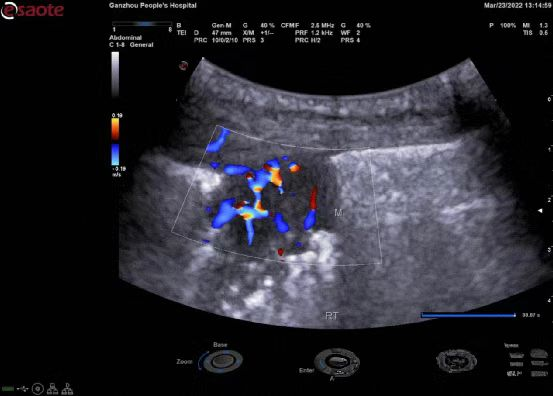

02

双平面腔内探头:

1.凸阵-线阵组合,微凸探头大角度可视范围

2.微凸探头扫查频率:3-13MH,线阵探头扫查频率:3-13MHz

3.穿刺架应用:经会阴前列腺穿刺(有效避免经直肠穿刺所致出血及感染等风险)

4.临床应用:泌尿科、肛肠科、介入科等

5.泌尿科应用:前列腺检查及穿刺活检,放射粒子植入。